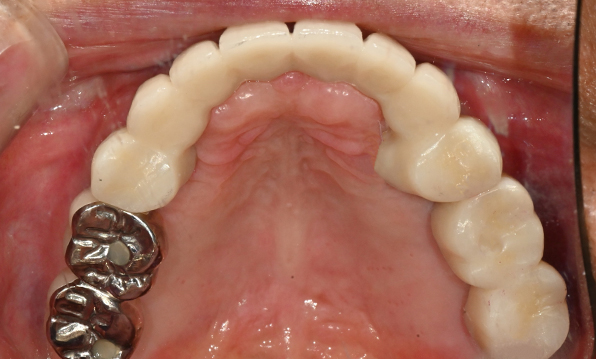

Case 02

Before After